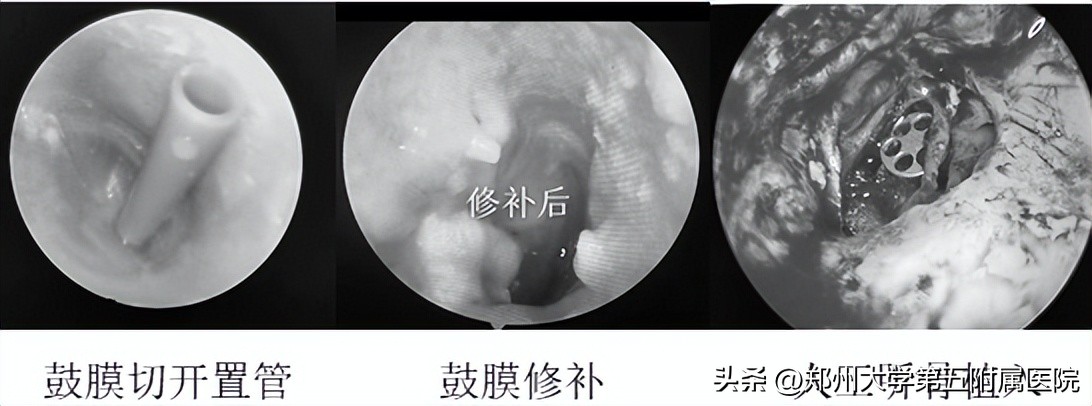

慢性单纯性中耳炎要减少诱因,避免急性中耳炎发作。如果反复耳朵流脓或者有听力减退等现象,也需要及时接受手术治疗。对于慢性分泌性中耳炎、骨疡性中耳炎、中耳胆脂瘤患者,需要尽早手术治疗。